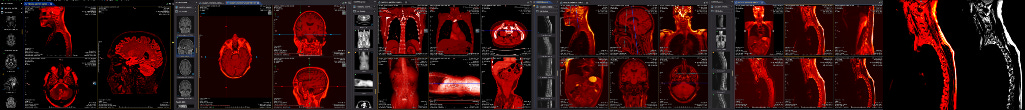

This post concerns an impending death; my own. My recent diagnosis (Mar 4ᵗʰ) is both complicated, but also typical of a stage four lung cancer (metastatic cancer), if I understand it right, with the cancer identifying itself only weeks ago, and further growths identified since then: I have tumours in the legs, lymph nodes and adrenal glands; a 4.5 cm tumour on the left lung is crowding out the nearby aorta; it has sprouted a smaller (11 mm) tumour on the right lung too; and colonies have set up camp in the cerebellum. A round of CT (Computed Tomography), MRI (Magnetic Resonance Imaging), X-Ray, EBUS (Endobronchial Ultrasound), and PET (Positron Emission Tomography) scan results is still being analysed. New facts emerge. I’m only just weeks into things and counting.

A PET scan is organised a few days later, at St Barts Hospital, in the shadow of St Paul’s. The body is flooded with a tracer radioactive fluid, after which you are locked into a lead-lined box for three-quarters of an hour to allow it to bake in. The scanner then detects where the tracer has been absorbed by cell growth anywhere in the body it is directed, producing reams of flowing light captured to film, copies of which—scans of my own body—are used throughout this post.

The moment I saw the very first scan the doctors showed me (bottom right, above: an MRI, rather than PET, as it happens)—on a small monitor wheeled into my cubicle at the Homerton—seemed to say everything at once. As I turned my head to look at the image of my brain on the monitor, I glimpsed also the tattoo on my left arm suddenly aligned with it (bottom left)—a tattoo of a bhikkhu meditating in flames, inked twenty years earlier, with the bhikkhu meditating as descibed in the Buddha’s Adittapariyaya Sutta (Fire Sermon)—such that the tattoo of the bhikkhu and the scan of the brain, aligned properly. One presaged the other by years, holding out its hand to the other. They reflected each other so neatly, with the tumour in the cerebellum showing up as the red-orange fire bursting through from within, which the bhikkhu sits through.

On seeing further scans, I recognised, eg., my rib cage as something indeed very much like the frame of Israel’s tents (above, top left), beaming on the shore of the infinite (Blake), but also, in the twisting images of the torso, I am struck by the sprawling energies at play, unleashed by disease. No longer is there the assumed underlying durable person, sealed away from the totality, cybernetically establishing their personal border by fending off and repurposing the chaos, sickness and disorder without. Instead, raw energies start to coalesce, turning Urizenic, mechanical rigidity into flashes, streaks and pulses of contending light.

scarlet rain falling: libelling the dead

In looking at the scan images in this post, try to imagine just how surprised I have been to realise that some 2-3 years ago I started working on a long (for me) poem/collage construction, which, for reasons I cannot explain (are there ever any such tidy reasons), I called Scarlet Rain. I have worked on it patiently for some time now.

You will see from the examples above that I am soon talking of lungs and jaws, ‘Easington irradiation’, blooming bones and the ‘undead bloodsuck’. The work currently stands at more than seventy pages, but remains unfinished. It includes many vignettes and side glances at my family history, as well as thoughts on ‘libelling the dead’.